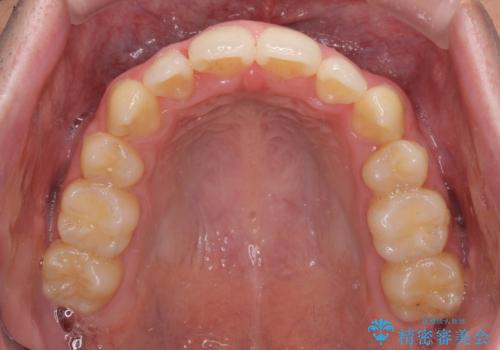

奥歯の咬み合わせの左右差が大きかったため、変則的な抜歯矯正を行いました。

治療期間はやや長期化しましたが、満足のいく歯並びとなりました。